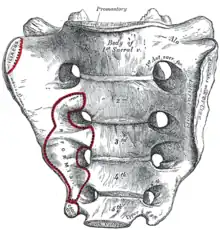

Origine

Le muscle piriforme se fixe sur :

- la face antéro-latérale du sacrum entre les 2e et 3e foramens sacrés antérieurs par trois digitations,

- la face antérieure du ligament sacro-tubéral.

Sacrum, face antérieure.

Sacrum, face antérieure. Extrémité supérieure du fémur vue d'en dedans.